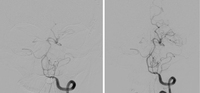

Distal left vertebral and basilar arteries spasm before (left) and after (right) intra-arterial infusion of nicardipine

Courtesy of Dr Salah Keyrouz; used with permission